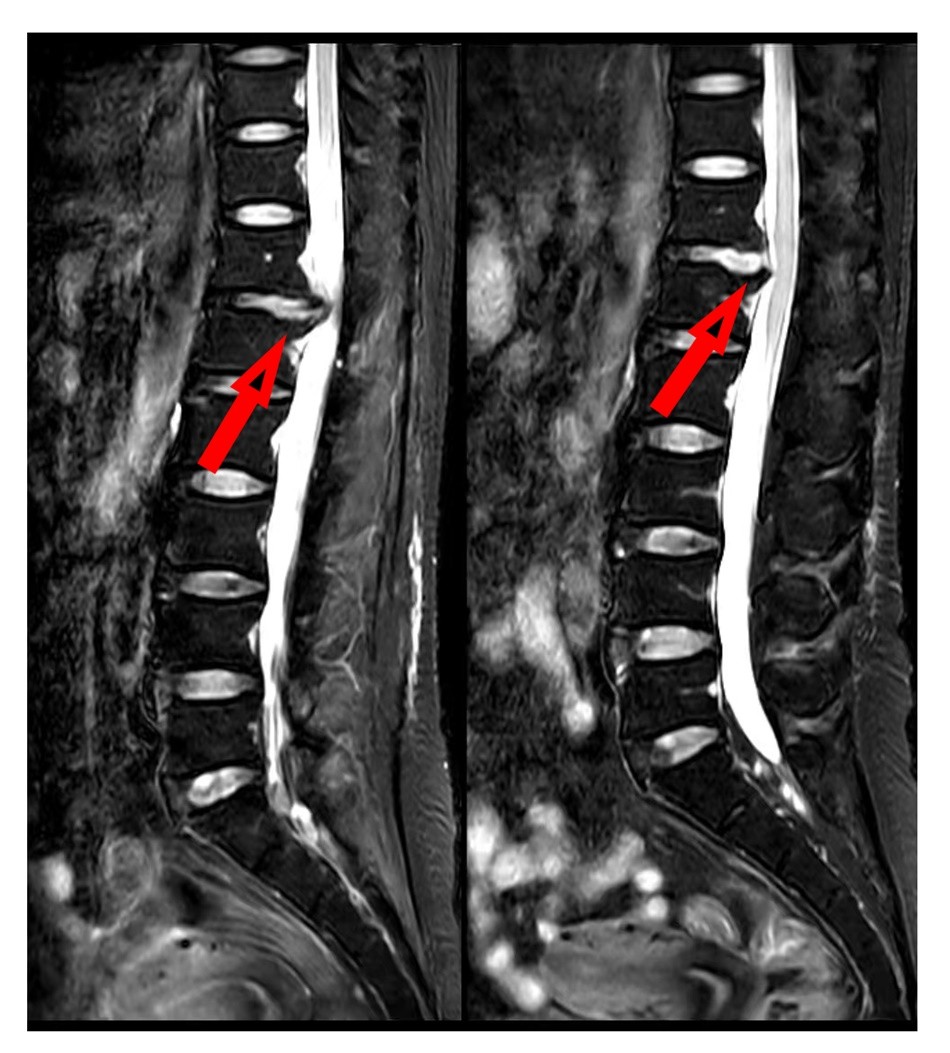

图1.术前(左图)术后(右图)腰椎磁共振矢状位对比,显示突出髓核已被摘除。